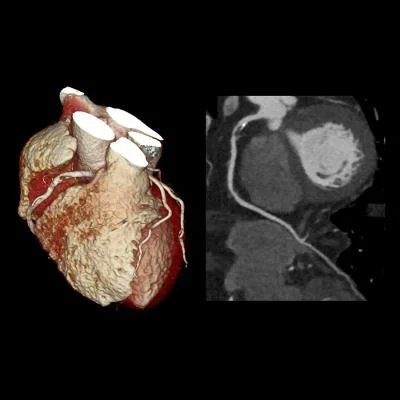

A cardiac CT is a scan of the heart and coronary arteries to assess for the presence and extent of advanced atherosclerosis.

There are two types of cardiac CT:

CT Coronary Artery Calcium scan. CT CAC Scan.

CT Coronary Angiogram. CTCA.